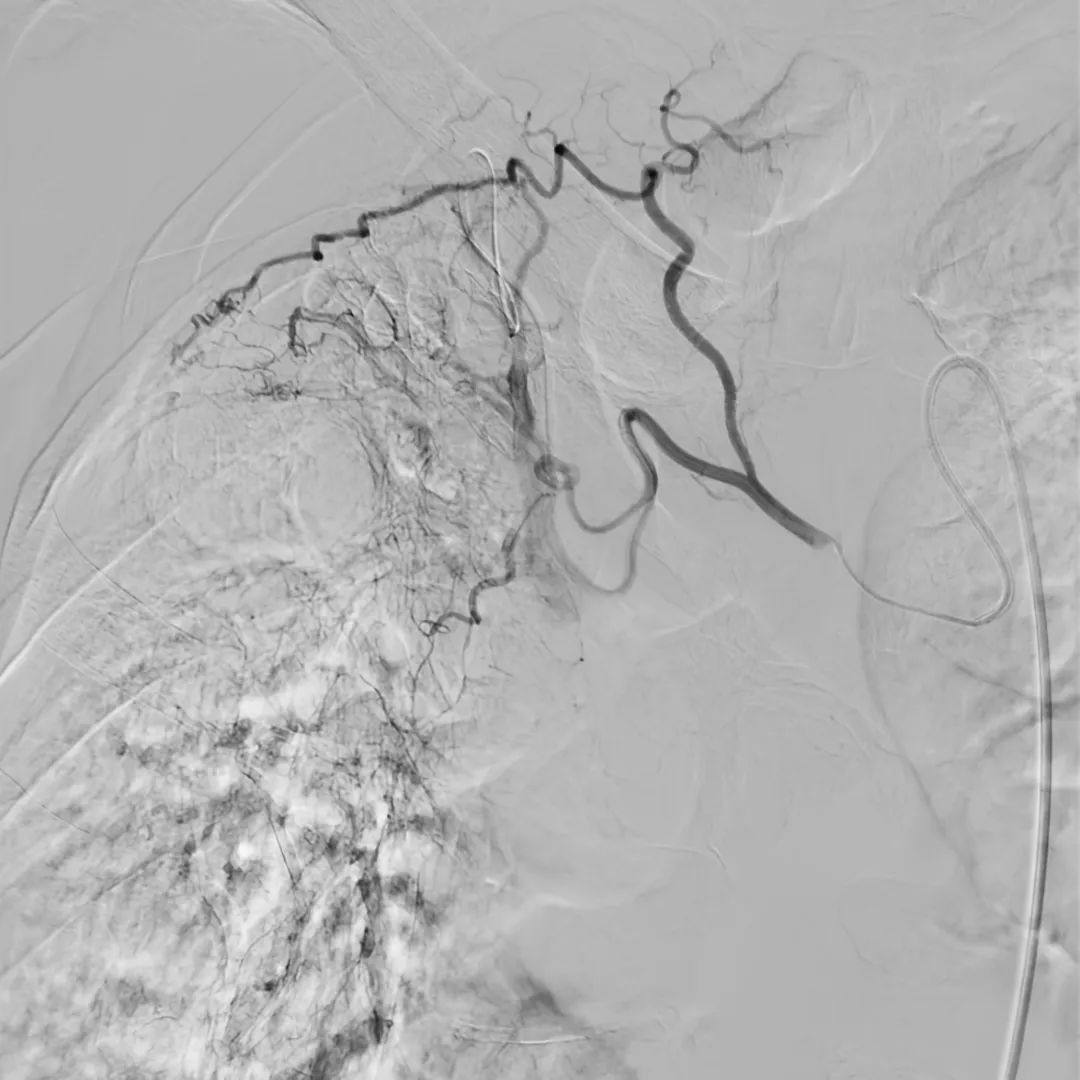

目前,唯邁醫(yī)療的DSA已裝機(jī)眾多三甲醫(yī)院,而剛剛完成裝機(jī)的濟(jì)南三院也在數(shù)日內(nèi)完成幾十例介入手術(shù),涵蓋經(jīng)介入造影治療,外周血管造影治療,心臟造影支架置入,滿足臨床多科室使用。

肝動(dòng)脈造影治療

下腔靜脈+濾器